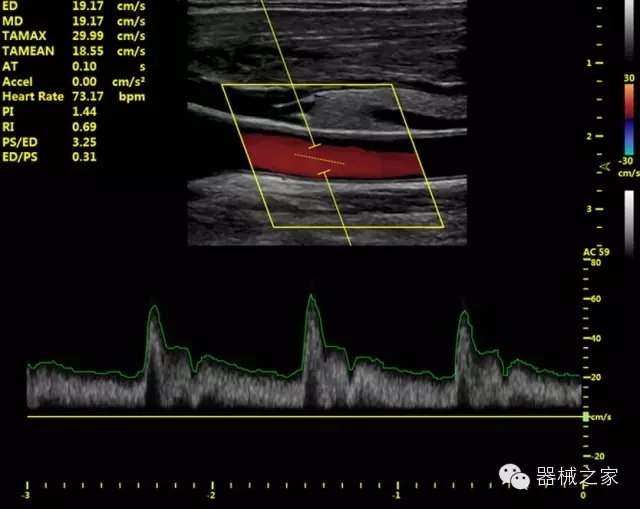

臨床圖片賞析

·IMT血管內(nèi)中膜自動測量:為血管性疾病評估提供了有效的評估手段;